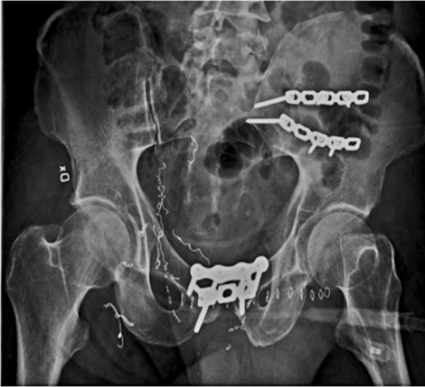

• Främre tillgång ovan symfys, genom inguinalkanal och/eller över bäckenvingen, varvid man kan nå hela främre delen av bäckenringen till och med sakroiliakaleden (Figur 5). Sakrumfrakturer är inte tillgängliga med dessa snitt.

• Bakre tillgång fås med perkutan osteosyntes eller öppet med dorsal snittföring i medellinjen, vid bakre kristakanten eller höftens baksida.

Vissa gravt dislokerade frakturer kräver ibland en kombination av flera tillgångar.